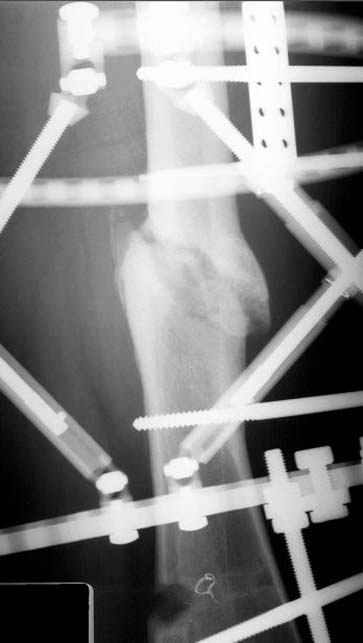

Несколько снимков из моей коллекции, чтобы разьяснить, почему мы до сих пор делаем различные варианты остеотомии.

N3 рисунок окончательный снимок, после операции моя рентгенограмма должен выглядеть примерно как эта картина. На N4 снимке клин перед удалением; N5 послеоперации 3 нед.; N6 окончательная рентгенограмма.

пластическая модель; и коррекция бедра аппаратом Илизарова.

Почему не замена гвоздя с рассверливанием, а аппарат?

Отправитель: Alexander Chelnokov 23 Ноябрь 2004, 21:29

хотя даже если бы и инфекция , то nail exchange с рассверливанием канала - вариант дебрайдмента) Я думаю, что последовательность развития событий:

Узкий к-м канал - тонкий гвоздь- усталостный перелом дистальных винтов - развитие нестабильности и как ее результат остеолиз вокруг гвоздя - деформация анатомической оси бедра. Похоже, что я понял почему аппарат, а не новый гвоздь:-)

ЕТ - Изначально костно-мозговой канал бедра был узкий, дальнейшее его рассверливание ещё больше скомпрометирует прочность бедра( латеральный кортекс дистального отломка уже истончен), приведет к дефекту наружной стенки - хотя это только мои догадки - хотелось бы знать мнение Джолдаса о выбранной тактике.